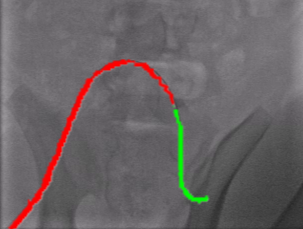

Qualitative Results. Fig. 5 illustrates the catheter and guidewire segmentation results of fine-tuning ViT on our method and different foundation models. The visualization portrays that our method excels in accurately delineating the catheter and guidewire structures, showcasing superior segmentation performance compared to other approaches. This figure further confirms that we can successfully train a federated endovascular foundation model without collecting users’ data and the trained foundation model is useful for the downstream segmentation task.

|

Animal |

Phantom |

Simulation |

Input

Ground Truth

LVM-Med

SAM

CLIP

Ours